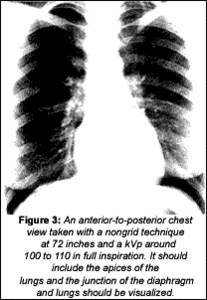

There are attorneys specializing in the laws pertaining to occupational diseases; there is also an International Classification of Radiographs of the Pneumoconioses, and many radiologists specialize in just the field of study related to this reference set. My point here is not to give information regarding asbestos exposure, but to impress upon you the importance of taking appropriate thoracic views. If your intention is to perform a thoracic spine study, use collimation to view the spine better. If your intention is to take a chest view, then use the proper technique for chest views.

As you can see, these are very different views, and the techniques are very different. Many of us do not have our x-ray rooms set up to perform chest views. Our rare earth screens are not intended to be used for performing P-A chest views. It is too easy to miss lesions, even on very good studies of the chest. If you are interested in improving your technique, there are many references available; some written by chiropractors, and some that may be accessed through chiropractic colleges. If you are having any problems with your x-ray unit or processing, contact your local supplier to help you. If you are still having problems, call your nearest DACBR or the radiology department at a chiropractic college; any one of them will help you with your technique problems. Many times, it is just a matter of chemistry or changing your kVp.